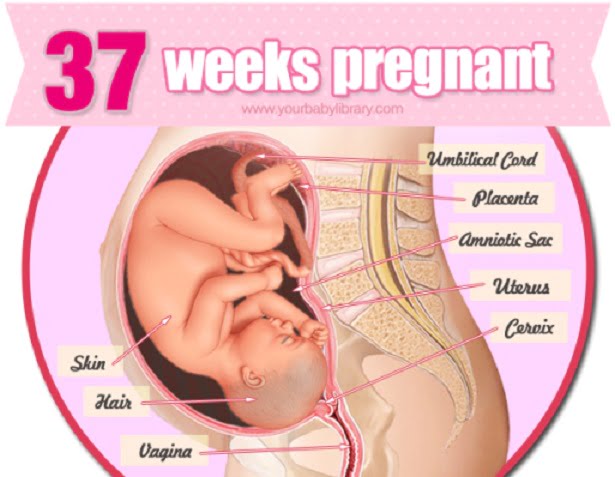

هفته سی و هفتم بارداری با انتقال آنتی بادری از بندناف به جنین همراه است. با نکات بارداری هفته به هفته و هفته سی و هفتم بارداری آشنا شوید.

فرزند درحال رشد شما در هفته سی و هفتم بارداری

بند ناف در پروسهی آماده شدن برای زایمان شروع به انتقال آنتی بادیها از بدن شما به جنین مینماید. با ذخیرهی آنتی بادیها، بدن فرزندتان بهتر میتواند با بیماریها و آلودگیهای فضای خارج از رحم روبرو گردد. حواس مختلف فرزندتان نیز در حال بهتر شدن و دقیقتر شدن هستند. فرزندتان میتواند شما را از روی صدایتان بشناسد. هنگامی که به دنیا آمد، خواهید دید که سرش را به سمت صدای شما میچرخاند. او مادرش را میشناسد! علاوهبر شنوایی، حس بینایی او نیز هر روز درحال بهتر شدن است. انگشتان او نیز در حال هماهنگتر شدن هستند. اکنون میتواند صورت و انگشتان خود را در دست بگیرد و پس از به دنیا آمدن قادر خواهد بود انگشت شما در در دست بگیرد.

سایز جنین: طول 35.5 سانتیمتر فاصلهی تاج تا کفل

طول کل 53.3 سانتیمتر

وزن 2950 گرم.

مرحلهی رشد جنین: فرزند شما به طور کامل تکامل یافته است.

آنچه در درون اتفاق میافتد؛ فرزند شما در هفته سی و هفتم بارداری

اگرچه فرزند شما اکنون کاملا تکامل یافته است، اما هنوز میتواند از چند روز بیشتر باقی ماندن در رحم بهرهمند گردد. او اکنون وزنی در حدود 2700 گرم و قدی بیش از 50 سانتیمتر دارد.با این حال حتی پزشک شما نیز نمیتواند با دقت وزن فرزند شما را حدس بزند زیرا بخشی از وزنی که شما اضافه کردهاید مربوط به مایع آمنیوتیک و افزایش حجم سینهها و رشد جفت است.

در واقع احتمالا با اینکه وزن شما بیشتر از این بالا نمیرود، فرزندتان همچنان به اضافه کردن وزن ادامه میدهد. در ادامهی روزهایی که از بارداریتان باقی مانده است، فرزند شما روزانه در حدود 14 گرم چربی به بدن خود اضافه مینماید. همزمان با این اتفاق بخشی از مایع آمنیوتیک درون رحم شما توسط بافتهای بدنتان جذب شده میزان مایع در اطراف جنین را کاهش میدهد. ممکن است اینطور احساس نمایید که فرزندتان نسبت به قبل تحرک کمتری دارد اما او همچنان به اندازهی قبل به تحرکات خود ادامه میدهد. همزمان با کشیدهتر شدن رحم، نور بیشتری به درون رحم نفوذ مینماید و جنین چشمهایش را به سمت این نور حرکت میدهد.

در این مرحله در حدود 3 درصد از جنینها در وضعیت بریچ باقی ماندهاند. ممکن است در این مرحله پزشک شما با انجام یک آزمون لگنی به بررسی حالت قرارگیری جنین بپردازد؛ پاها، باسن و سر در این مرحله به آسانی قابل تمییز دادن هستند.

در این هفتهها (یا روزهای) پایانی بارداری بدن شما و فرزندتان درحال آماده شدن برای فشار زایمان است. بند ناف با انتقال آنتی بیوتیکها به بدن جنین او را برای زایمان آماده میکند. بدن فرزند شما با ذخیره کردن آنتی بیوتیکها خود را برای مقابله با بیماری ها و میکروبهایی که پس از زایمان با آنها روبرو میگردد مهیا میکند.

وزن اضافه شدهی نوزاد نیز به بقای او در محیط بیرون و به رشد او کمک میکند. بدن نوزاد اکنون که دیگر از محافظت لایههای رحم و مایع درون کیسهی آمنیوتیک بهرهمند نیست نیاز به یک لایهی عایق و محافظ دارد. اکنون بدن او به تنهایی مسول محافظت در برابر سرما و گرما خواهد بود.

اکنون فرزندتان میتواند صدای شما را به خوبی تشخیص دهد. پس از تولد مشاهده خواهید کرد که فرزندتان سرش را به سمت صدای شما برگردانده نسبت به آن واکنش نشان میدهد. او مادرش را میشناسد! علاوه بر شنوایی، قدرت بینایی او نیز روز به روز درحال افزایش است. انگشتان دستش با هم هماهنگتر شدهاند. او میتواند صورت خود و انگشتان پایش را چنگ بزند و پس از تولد قادر خواهد بود انگشت شما را در مشت خود بفشارد.